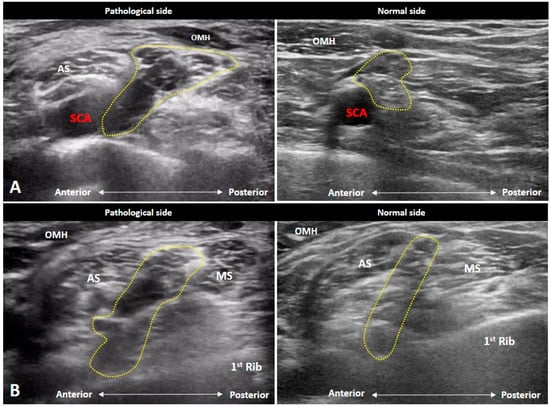

4.5. Thoracic Outlet Syndrome

5. Conclusions